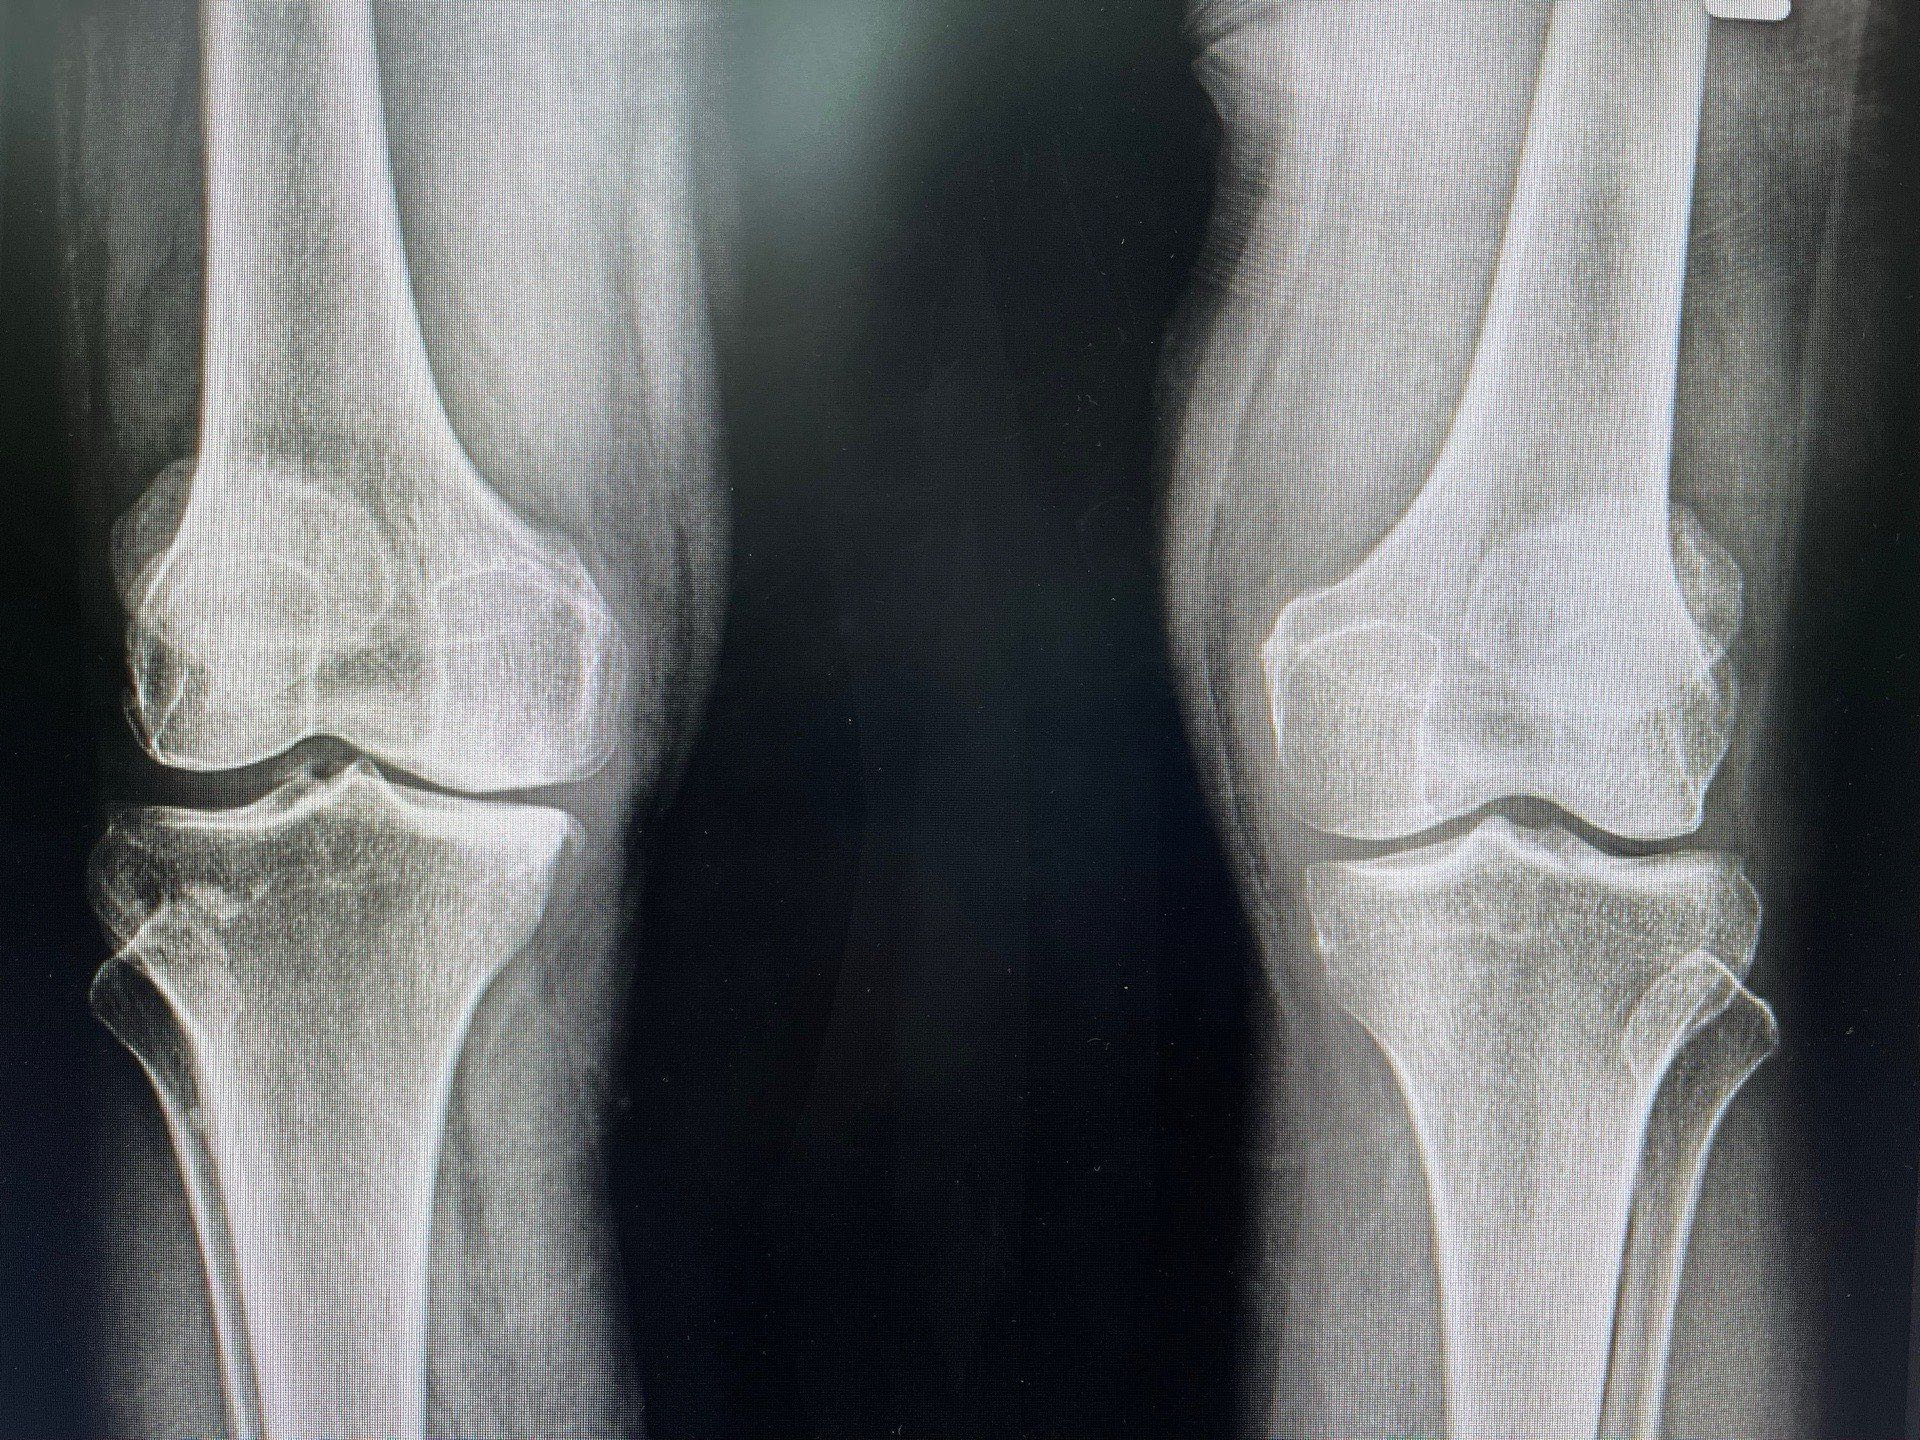

2. โรคข้อเสื่อม (Osteoarthritis)

• สาเหตุ: เกิดจากการเสื่อมของกระดูกอ่อนในข้อที่เกิดขึ้นตามวัย หรือจากการใช้งานข้อมากเกินไป เช่น การนั่งหรือยืนนานๆ การออกกำลังกายหนัก

• อาการ: อาการปวดจะค่อยๆ เกิดขึ้นและรุนแรงมากขึ้นเมื่อมีการใช้งานข้อ เช่น ตอนเดิน ยืน หรือทำงานที่ใช้ข้อมากๆ มักพบในข้อเข่า ข้อสะโพก และกระดูกสันหลัง

• กลุ่มเสี่ยง: ผู้สูงอายุ หรือผู้ที่มีน้ำหนักตัวมาก ซึ่งทำให้ข้อเข่าต้องรับน้ำหนักเยอะ

• ลักษณะอาการเฉพาะ: ปวดเรื้อรังและค่อยๆ รุนแรงขึ้น ข้ออาจแข็งหรือลั่นเสียงกรอบแกรบเวลาขยับ